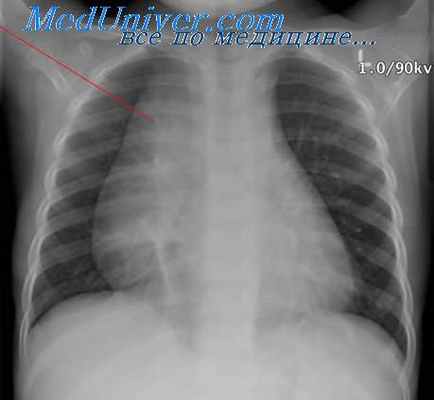

Если вы посмотрите на обзорный снимок в прямой проекции, то сразу же будет видно, насколько изменилась конфигурация воздушного столба в трахее на уровне грудино-ключичных расчленений и выше в области верхней апертуры. Трахея оттеснена по дуге вправо и практически достигает контура средостения и несколько сужена.

Небольшое патологическое образование, которое по форме напоминает нисходящую часть аорты в поперечном сечении. Бессимптомное течение. Обычно 3-я или 4-я декады жизни, округлая форма, четкие контуры, тканевая плотность. Очень часто кальцификация, кисты. Самое главное – абсолютно типичная локализация в большинстве случаев в реберно-позвоночном углу.

В этом случае, даже если у нас есть обычное компьютерно-томографическое исследование, без всякого контрастирования, информации, локализация в заднем средостении, которая четко определяется по обзорным снимкам, проекция патологического образования на тень позвонков, которая позволяет нам говорить, что это образование находится в реберном позвоночном углу.